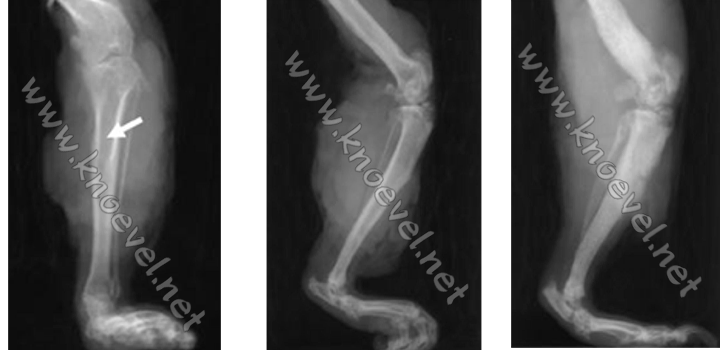

Hieronder ziet u de 3D reconstructie van een cavia achterbeen (scheenbeen, kniegewricht en dijbeen).

Niet satijn (ca. 6 jaar), satijn met beginnende OD (4 jaar), satijn met gevorderde OD (2 jaar)

Het is duidelijk dat de ziekte progressief de botstructuur aantast. De vervorming van het kniegewricht duidt op een ernstige artritis - het verklaart ook de pijn die OD patiënten moeten verduren. Het meest opvallende is echter de vorming van amorfe (poreuze) botmassa, en het ontstaan van gaatjes in het botoppervlak (zie onder). De nieuwe botmassa (rechter foto) doet ons denken aan bepaalde soorten botkanker bij mensen en andere dieren.